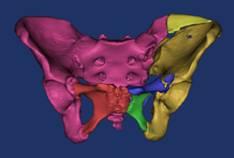

骨盆术前三维模型和模拟复位--正位前面观